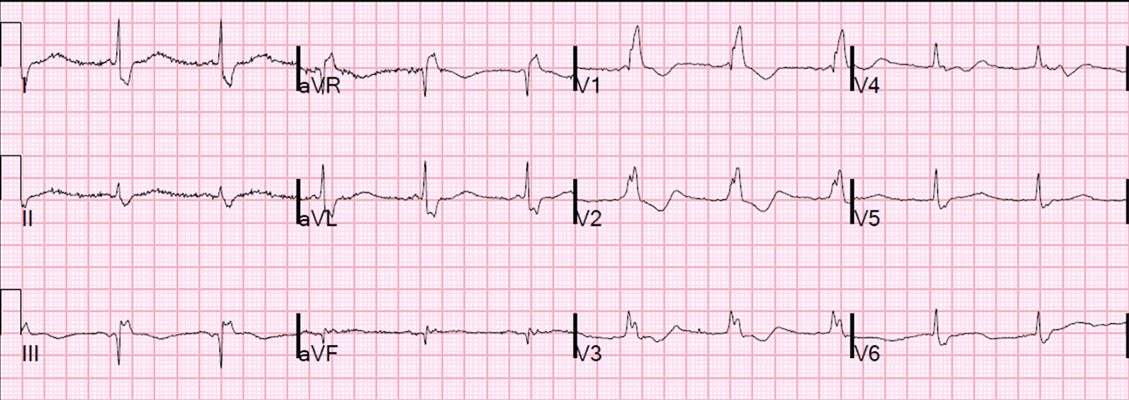

預激綜合徵心電圖 (82)

預激綜合徵心電圖 (83)

預激綜合徵心電圖 (84)

預激綜合徵心電圖 (85)

預激綜合徵心電圖 (86)

預激綜合徵心電圖 (87)

預激綜合徵心電圖 (88)

預激綜合徵心電圖 (89)

A:預激綜合徵典型的心電圖表現是竇性心搏的PR間期縮短,短於0.12s,而且導聯的QRS波群時間超過0.12s。QRS波群起始部分會有粗鈍,終末部分正常,甚至會導致ST-T波型呈現繼發性的改變,甚至於QRS波群主波方向相反。預激綜合徵是指心房……

A:預激綜合徵是很少見的心律失常,是房室傳導異常的一種類型,提早興奮心室的一部分或全部,引起心室肌提前激動,常合併室上性心動過速。心電圖可見PR間期縮短小於0.12秒;QRS時限延長0.11秒以上;QRS波群起始部粗鈍,繼發性ST-T改變。沒有……